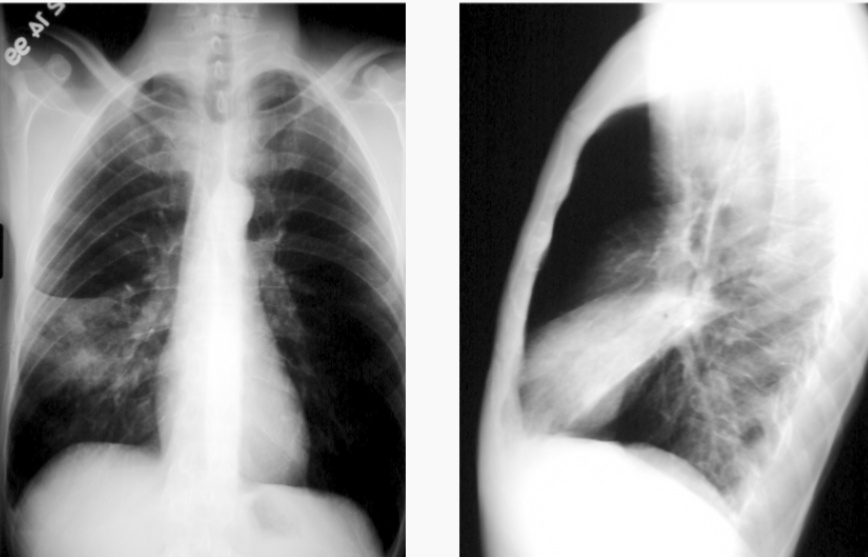

What is this patient presenting with?

Tension pneumothorax

(look out for mediastinal shift suggesting a tension pneumothorax)